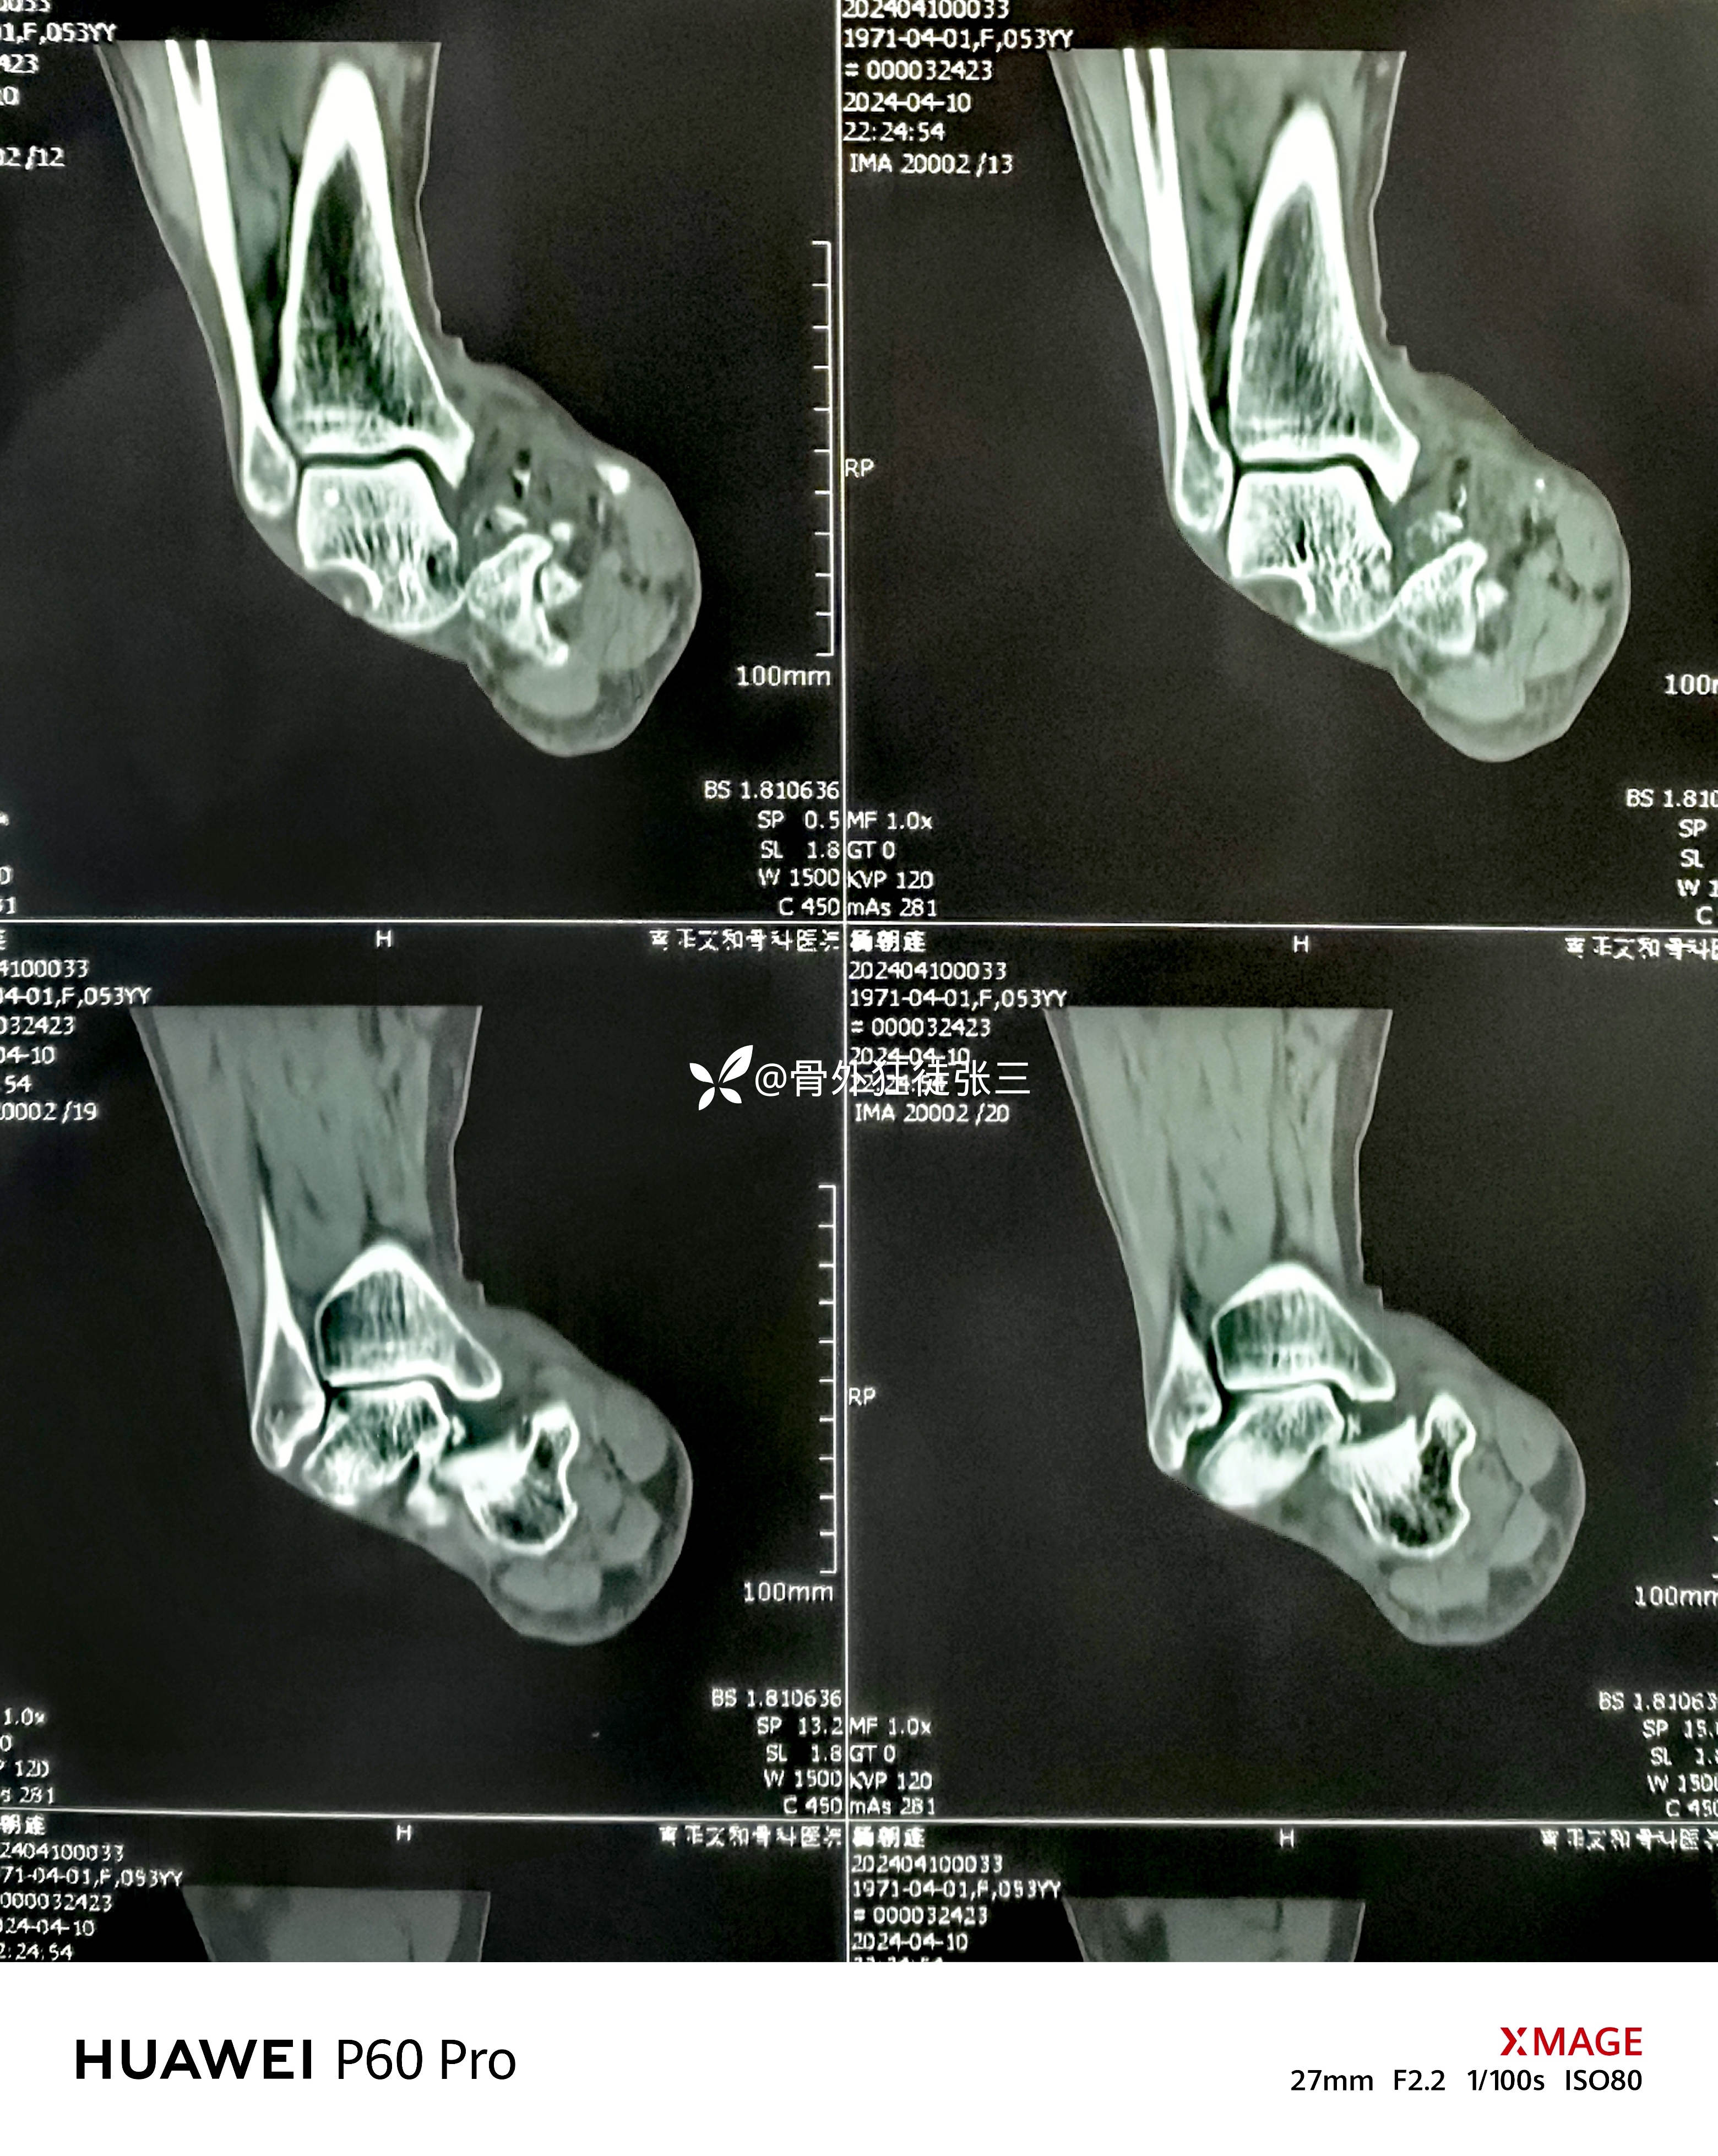

罕见损伤:距下关节脱位

主诉:车祸扭伤右踝关节致肿痛、畸形、活动受限1小时。

右踝关节肿胀明显,屈曲内翻畸形,活动受限。

右距下关节脱位(内侧型)